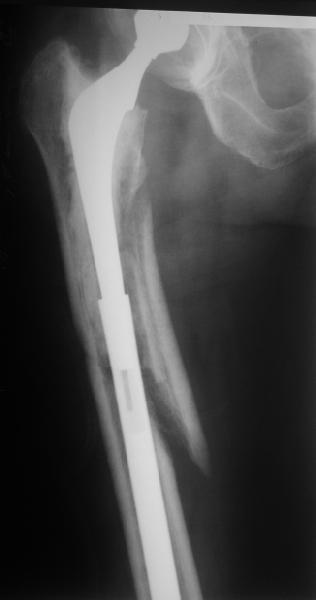

Female, rheumatoid, THA in 2003, car accident in 2006, failed plating. Nailing in Oct 2007. The nail is solid with hollow proximal part where the stem is docked. Last images are in 1 year after

nailing.